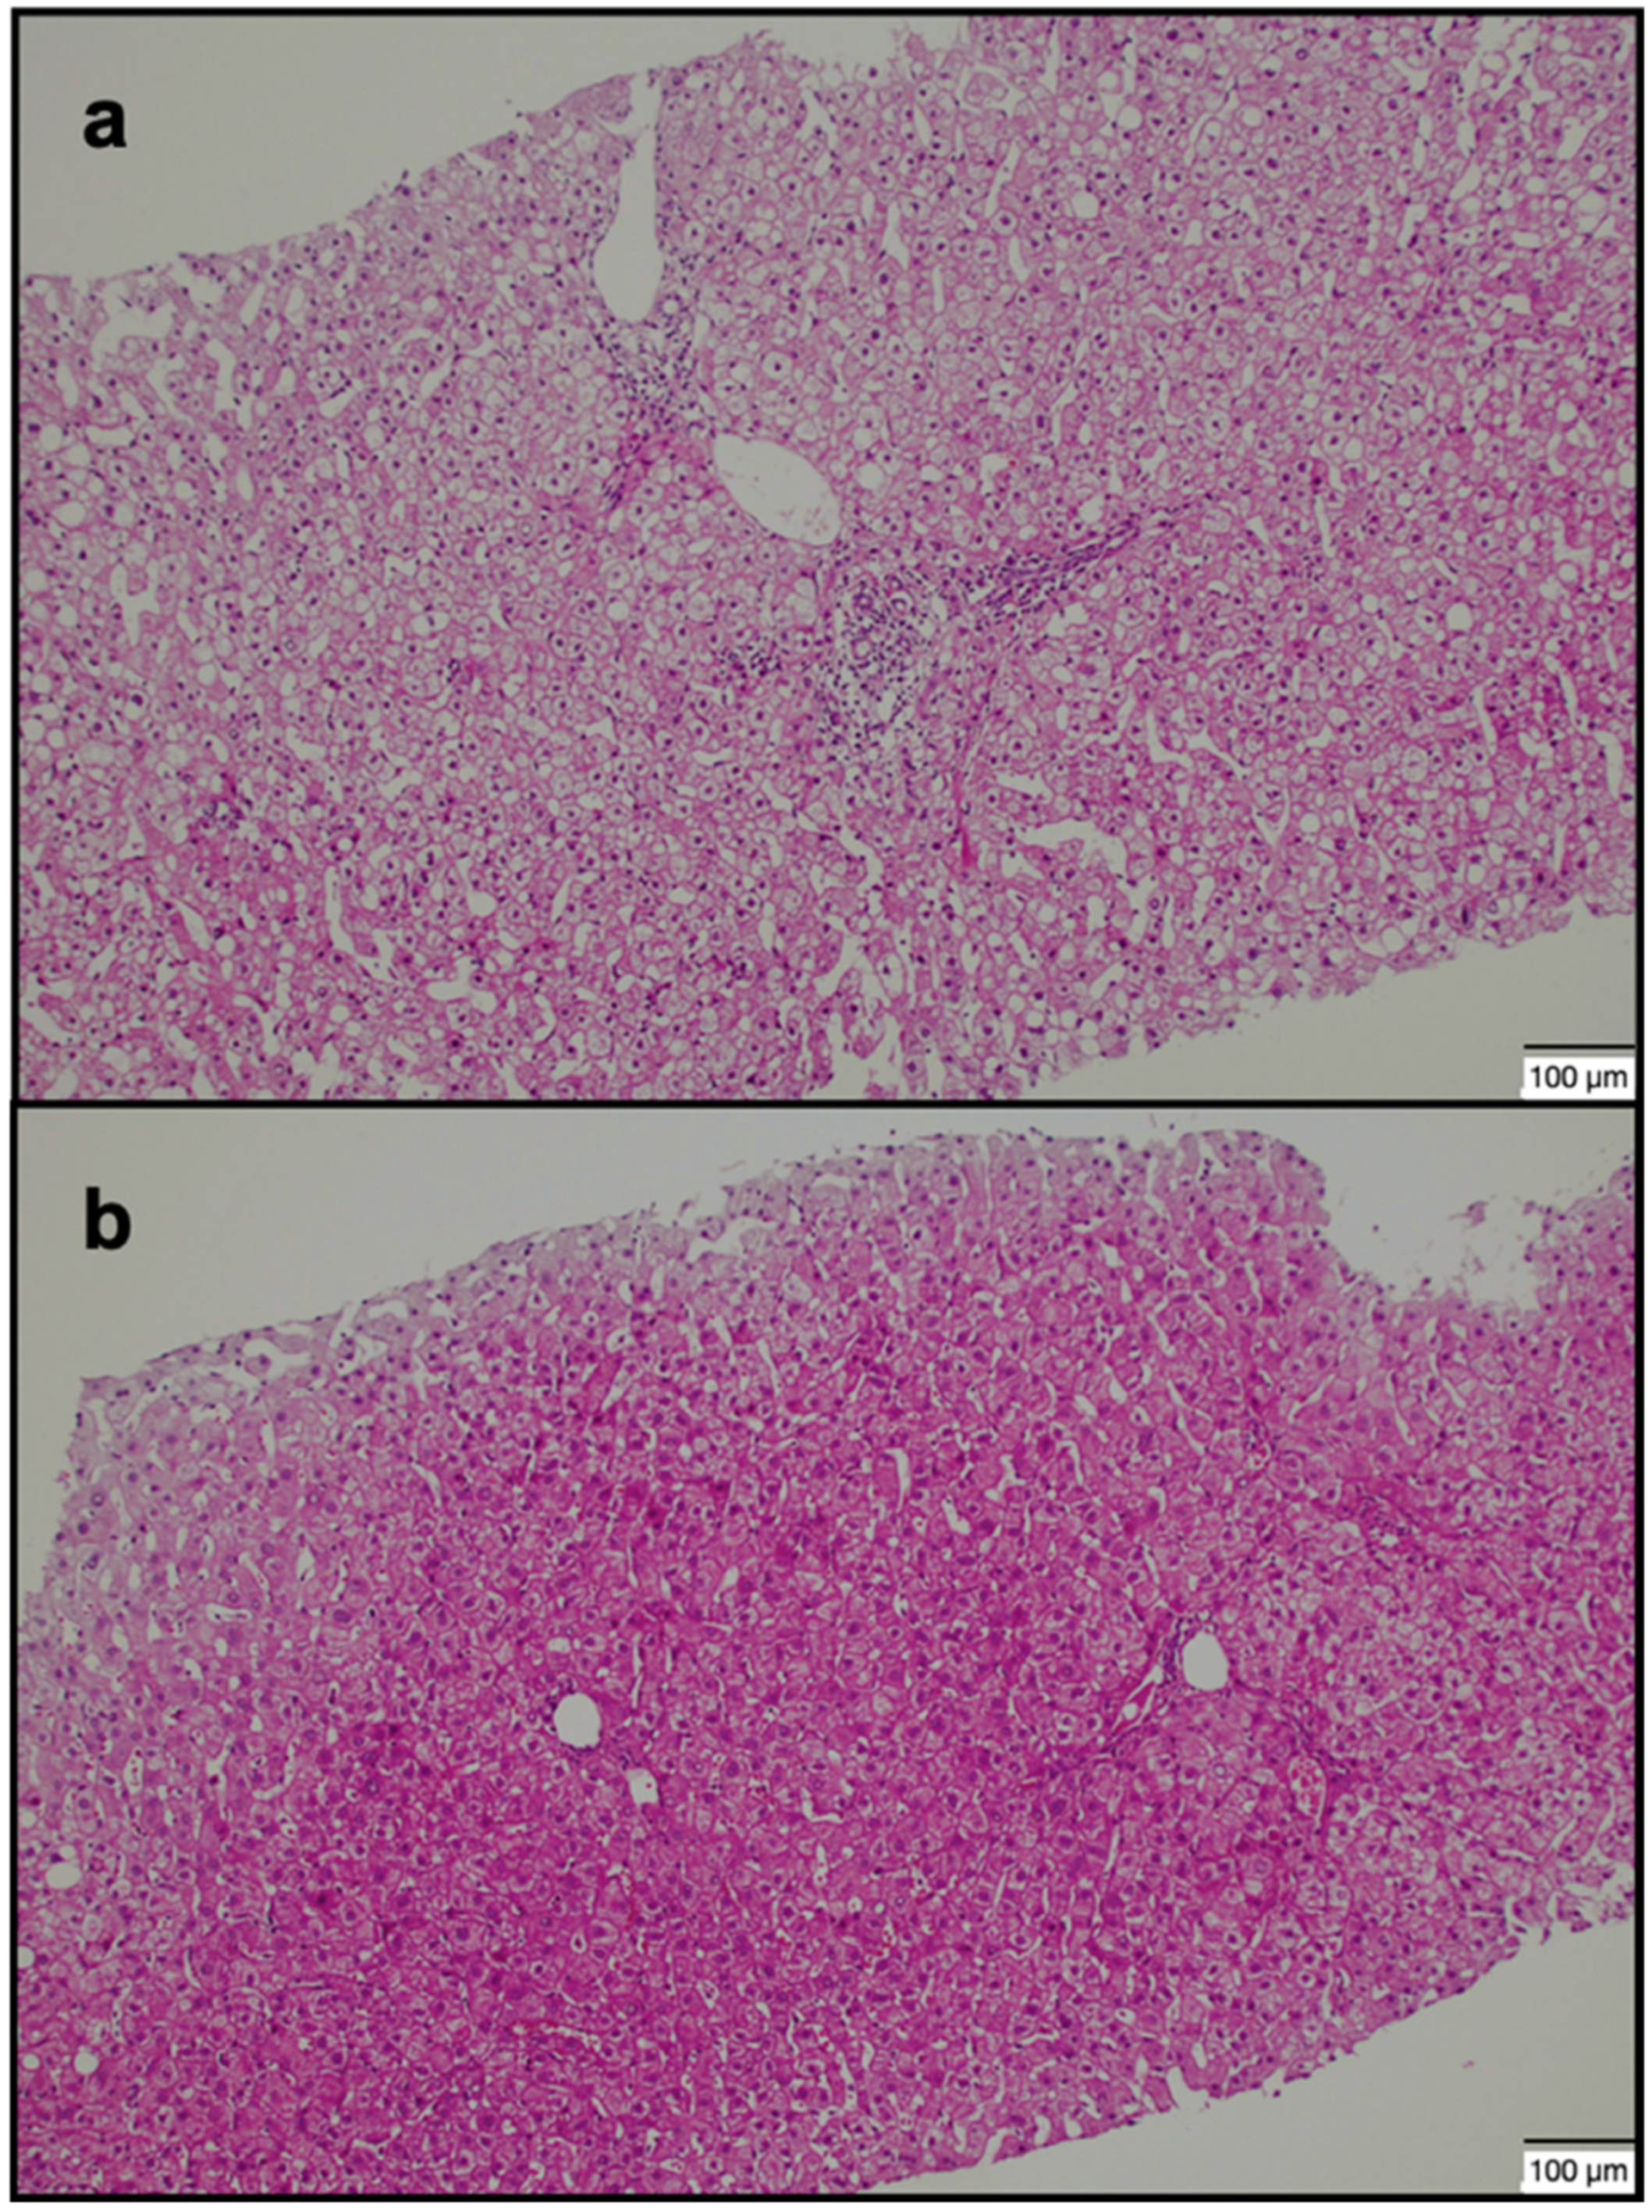

2.2. Image Analysis and Biopsy Procedure

| mHAI grade (≥5) | 20/40 | 22/40 | 0.654 |

| Fibrosis grade (≥2) | 17/40 | 20/40 | 0.501 |

| mHAI grade, mean (range) | 5.25 ± 2.63 (2–13) | 5.28 ± 2.63 (2–13) | 0.966 |

| Fibrosis grade, mean (range) | 1.70 ± 1.04 (0–5) | 1.75 ± 1.06 (0–5) | 0.832 |

| mHAI grade (≥5) | 30/40 | 12/40 | <0.001 |

| Fibrosis grade (≥2) | 28/40 | 9/40 | <0.001 |

| mHAI grade, mean | 6.28 ± 2.47 | 4.25 ± 2.37 | <0.001 |

| Fibrosis grade, mean | 2.20 ± 1.09 | 1.25 ± 0.74 | <0.001 |